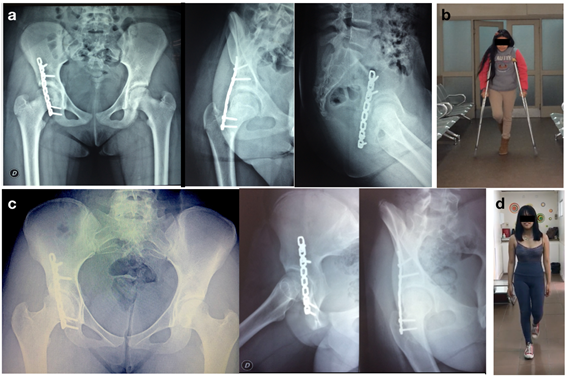

Presentó una excelente evolución postoperatoria inmediata, se permitió comenzar con apoyo parcial y progresivo, según tolerancia al dolor a las seis semanas logrando el apoyo total a las 12 semanas.

En los controles clínico - radiológicos seriados no se observó desplazamientos secundarios, tampoco el cierre prematuro del cartílago trirradiado ni otras complicaciones. El último control registrado a los cinco años de la cirugía presentaba una cadera asintomática, libre en todos los movimientos, sin restricciones para sus actividades cotidianas y radiológicamente simétrica a la contralateral. La valoración funcional final de la cadera fue excelente, fue realizada mediante el cuestionario de Harris Hip Score (HHS) obteniendo un puntaje de 100/100 (excelente 91-100; buena 81-90; aceptable 71-80; pobre 70 o menos).

Figura 2: a. Radiografías postOp inmediato, b. Foto clínica postOp. c. Radiografías a los 5 años postOp, d. Foto clínica 5 años portOp.